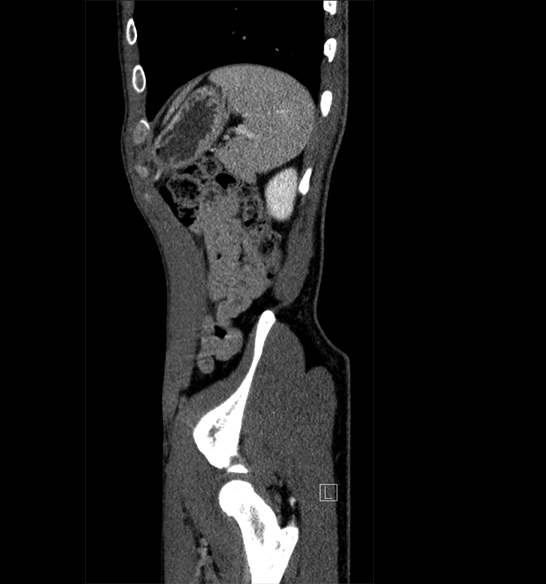

Body

Covers abdominal CT anatomy.